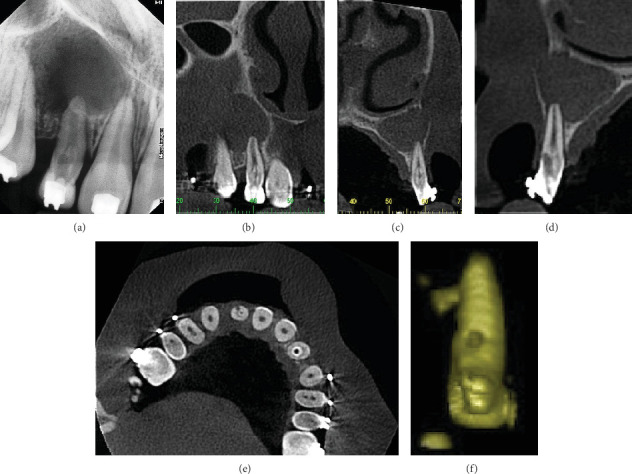

Dens invaginatus (DI) is a developmental anomaly that affects teeth. This case report demonstrates the successful endoaesthetic management of a Type II DI in the maxillary right lateral incisor (Tooth 12). A 12-year-old female patient presented with pain and swelling in Tooth 12, which had previously been diagnosed with DI and accessed endodontically. The patient was also concerned about the aesthetic appearance of her anterior teeth. Clinical, radiographic, and tomographic findings confirmed Oehler's type II DI, with root perforation and an apical abscess in Tooth 12, as well as pulp necrosis in Tooth 13. Nonsurgical root canal treatment was recommended for both teeth, with additional root perforation repair for Tooth 12. Multiple visits were required for nonsurgical endodontic therapy. During the initial visit, the perforation was identified and sealed, followed by chemomechanical preparation and placement of calcium hydroxide paste. Ten months later, the root canals were filled. After endodontic treatment, the patient underwent in-office bleaching, followed by composite resin veneers on the upper anterior teeth, using the preformed metal matrix technique. This resulted in excellent aesthetic outcomes. At the 2-year follow-up examination, the patient remained asymptomatic, and radiographic assessment showed complete resolution of the periapical lesion. This case highlights the importance of multidisciplinary collaboration, precise treatment planning, and patient-centered care in achieving optimal endoaesthetic results in complex cases.